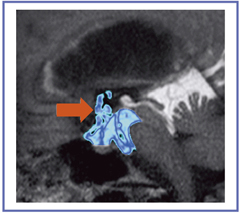

Aqueduct stenosisもTime-SLIP法がきわめて有用な症例で,髄液路の閉塞の有無だけでなく狭窄の程度まで描出でき,神経内視鏡によるETV(Endoscopic Third Ventriculostomy)後の開窓部開存率の確認(図12)も容易に可能である。